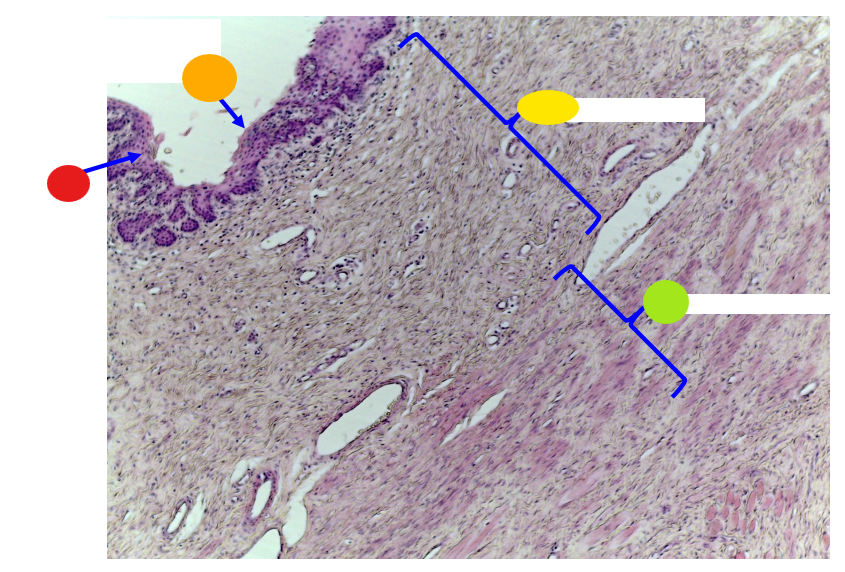

red

tunica albuginea

orange

primordial follicles

red

primary follicle

orange

secondary follicles

what is this

tertiary follicle